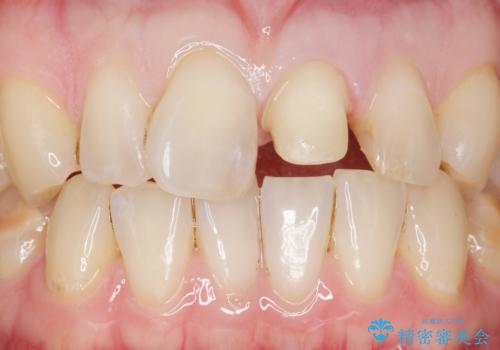

- 前歯のプラスチックの詰め物が気になると来院された患者様です。

左上の前歯に詰められたプラスチック(コンポジットレジン)は、劣化し変色していました。

レジンを除去したところ二次う蝕を認めたため、丁寧に虫歯をとりました。

歯の欠損範囲が大きいことから、同様にレジン修復しても欠けやすいためセラミッククラウンによる補綴を行いました。

患者様のご希望により、最終補綴前にホワイトニングを行いました。